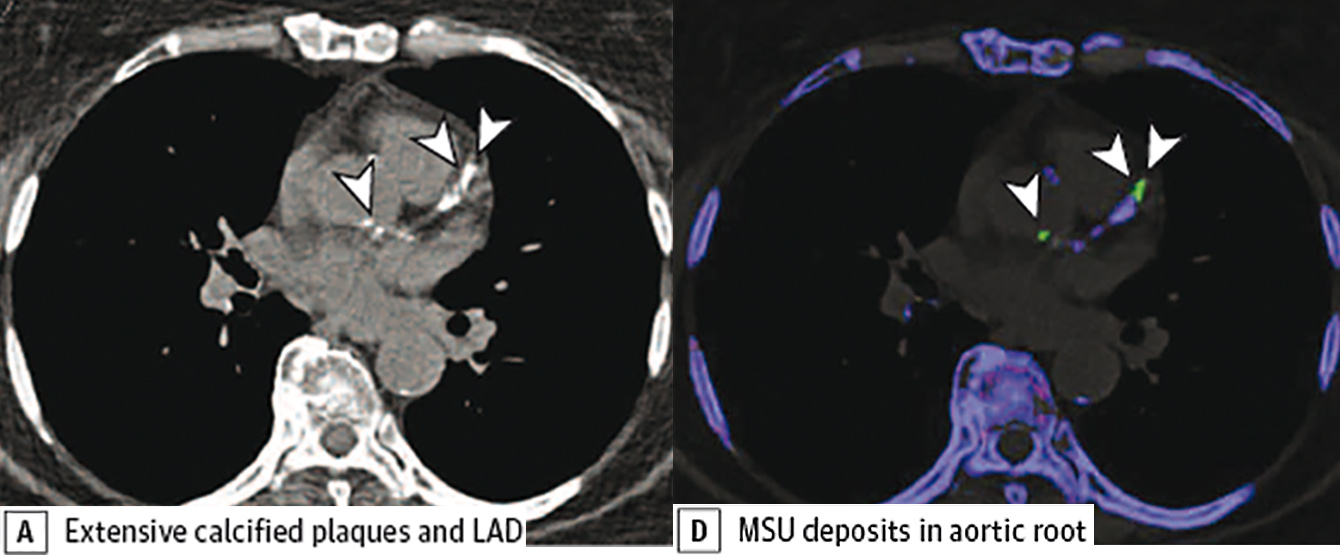

Im Bild: A natives CT zeigt deutliche Verkalkungen in der linken Koronararterie (weiße Pfeile), die sich violett in der DECT darstellen. Die grünen Ablagerungen entsprechen Uratablagerungen, die zwischengelagert sind. (Foto: Klauser/Univ.-Klinik f. Radiologie)

Das Auftreten von Gichterkrankungen nimmt in den letzten Dekaden zu. Verschiedene Studien haben bereits länger gezeigt, dass die Gicht als Risikofaktor für eine koronare Herzkrankheit im Zusammenhang steht. Bis dato war der Nachweis von Gichtkristallen in Geweben nur mittels Biopsie/Punktion und aufwändigen mikroskopischen Verfahren möglich. Die Arbeitsgruppe von Andrea Klauser von der Universitätsklinik für Radiologie (Direktor Werner Jaschke) erforscht bereits seit Jahren erfolgreich Gichtausfällungen in Gelenken mittels der Dual-energy-Computertomografie (DECT). „Für uns war es somit naheliegend, den Stellenwert dieser Bildgebungstechnik auch in der kardiovaskulären Bildgebung zu prüfen“, sagt Klauser. Für die Darstellung wird eine CT-Untersuchung mit zwei verschiedenen Strahlungsenergien durchgeführt. „Es wird ein CT-Gerät eingesetzt, das Zweienergiemessungen ohne relevante Erhöhung der Strahlendosis mit höchster Auflösung ermöglicht“, so die Radiologin. Das Hauptziel dieser ersten, kürzlich im JAMA Cardiology publizierten Studie, war die Prüfung der Möglichkeit von DECT im Nachweis von kardiovaskulären Harnsäureablagerungen (Uratablagerungen). „Dafür wurden DECT-Untersuchungen von Patienten mit Gicht und ohne Gicht prospekiv untersucht und die Untersuchungsergebnisse verglichen“, beschreibt Andrea Klauser die Vorgehensweise. Insgesamt wurden 59 Gichtpatient:innen (mittleres Alter 59) und 47 Kontrollen (mittleres Alter 70) untersucht.

Die Studie wurde in enger Zusammenarbeit mit der Universitätsklinik für Innere Medizin II (Direktor Günter Weiss) im Zeitraum von Jänner 2017 bis November 2018 durchgeführt. „Der Calcium Score der Koronargefäße, also der quantitativer Nachweis von Kalkablagerungen mittels CT, ist ein gut etablierter Marker für die Einschätzung des Risikos, an einer koronaren Herzerkrankung zu erkranken“, weiß Klauser. Deshalb wurde mittels CT simultan der Calcium score und die Uratablagerungen in den Koronorien und der Aorta gemessen. Darüber hinaus wurden in Kooperation mit dem Department für Anatomie, Histologie und Embryologie (Direktorin Helga Fritsch) DECT positive Proben von Uratablagerungen in Gefäßen mittels Polarsiationsmikroskop korreliert. Es wurde die neue Methode mit einem etablierten Verfahren (Biopsie) verglichen, um dadurch diagnostische Fehler auszuschließen.